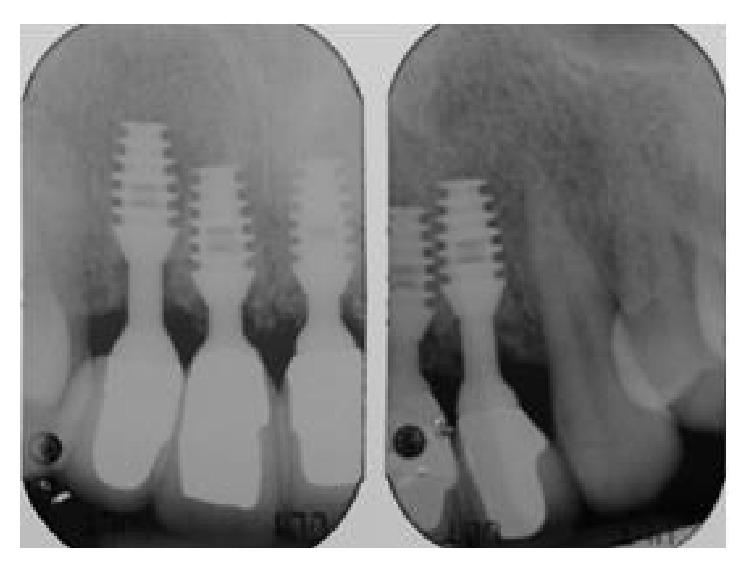

The functional and aesthetic restoration of teeth compromised due to aggressive periodontitis presents numerous challenges for the clinician. Horizontal bone loss and soft tissue destruction resulting from periodontitis can impede implant placement and the regeneration of an aesthetically pleasing gingival smile line, often requiring bone augmentation and mucogingival surgery, respectively. Conservative approaches to the treatment of aggressive periodontitis (i.e., treatments that use minimally invasive tools and techniques) have been purported to yield positive outcomes. Here, we report on the treatment and five-year follow-up of patient suffering from aggressive periodontitis using a minimally invasive surgical technique and implant system. By using the methods described herein, we were able to achieve the immediate aesthetic and functional restoration of the maxillary incisors in a case that would otherwise require bone augmentation and extensive mucogingival surgery. This technique represents a conservative and efficacious alternative to the aesthetic and functional replacement of teeth compromised due to aggressive periodontitis.

侵袭性牙周炎导致牙齿功能和美观受损,给临床医生带来诸多挑战。牙周炎引起的水平骨吸收和软组织破坏会妨碍种植体植入以及美观的牙龈微笑线的再生,通常分别需要进行骨增量和膜龈手术。据称,侵袭性牙周炎的保守治疗方法(即使用微创工具和技术的治疗方法)能产生积极效果。在此,我们报告了一名侵袭性牙周炎患者采用微创外科技术和种植系统的治疗及五年随访情况。通过使用本文所述方法,在原本需要骨增量和广泛膜龈手术的病例中,我们成功实现了上颌切牙的即刻美观和功能恢复。该技术是侵袭性牙周炎导致牙齿功能和美观受损时,一种保守且有效的替代治疗方法。